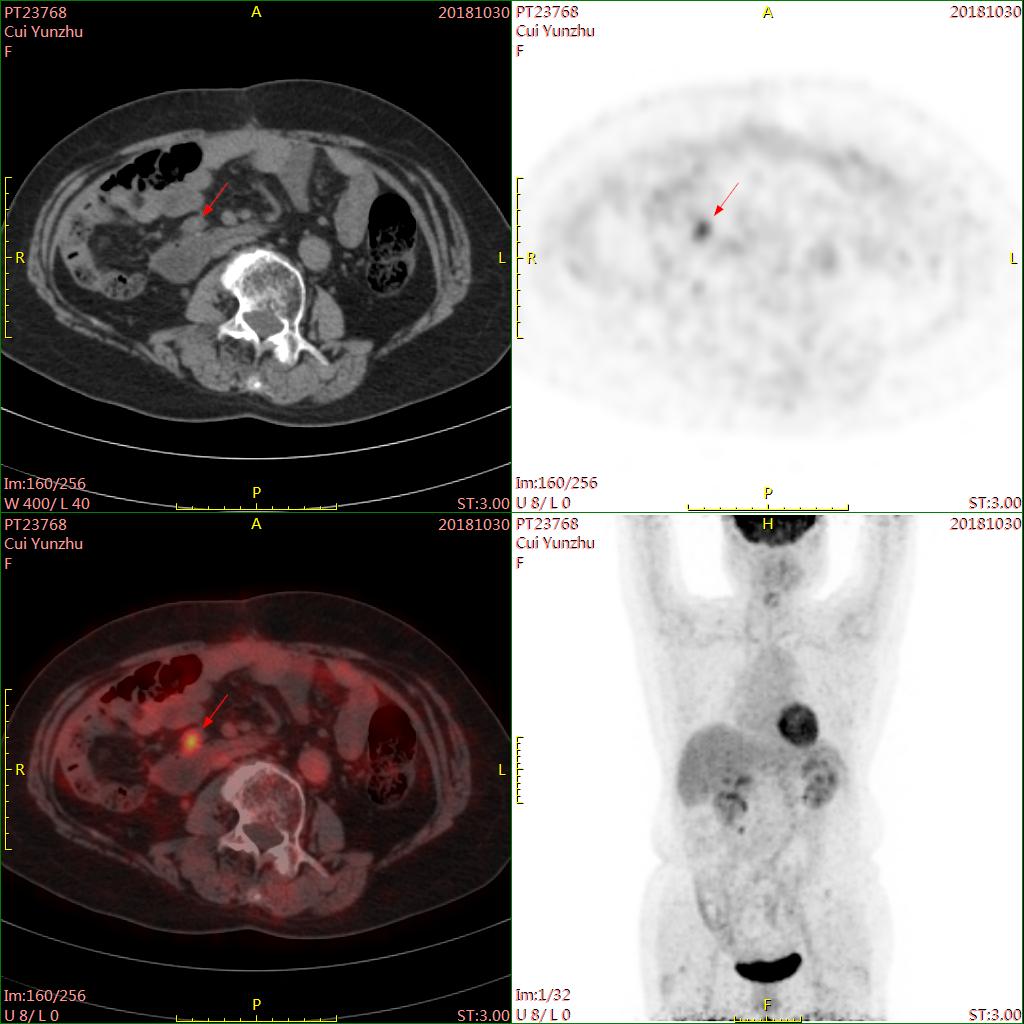

PET-CT:腹部肠系膜1cm×1.3cm结节,FDG代谢增高,考虑中腹部肠系膜转移。

肿瘤标检测:CA125:6.28;HE4:53.66(2018-10-30)。

PET-CT:中腹部肠系膜1.4cm×1cm结节,密度稍高,FDG代谢增高,相比无明显变化。

CA125:9.46。

HE4:66.21(2019-03-22)。